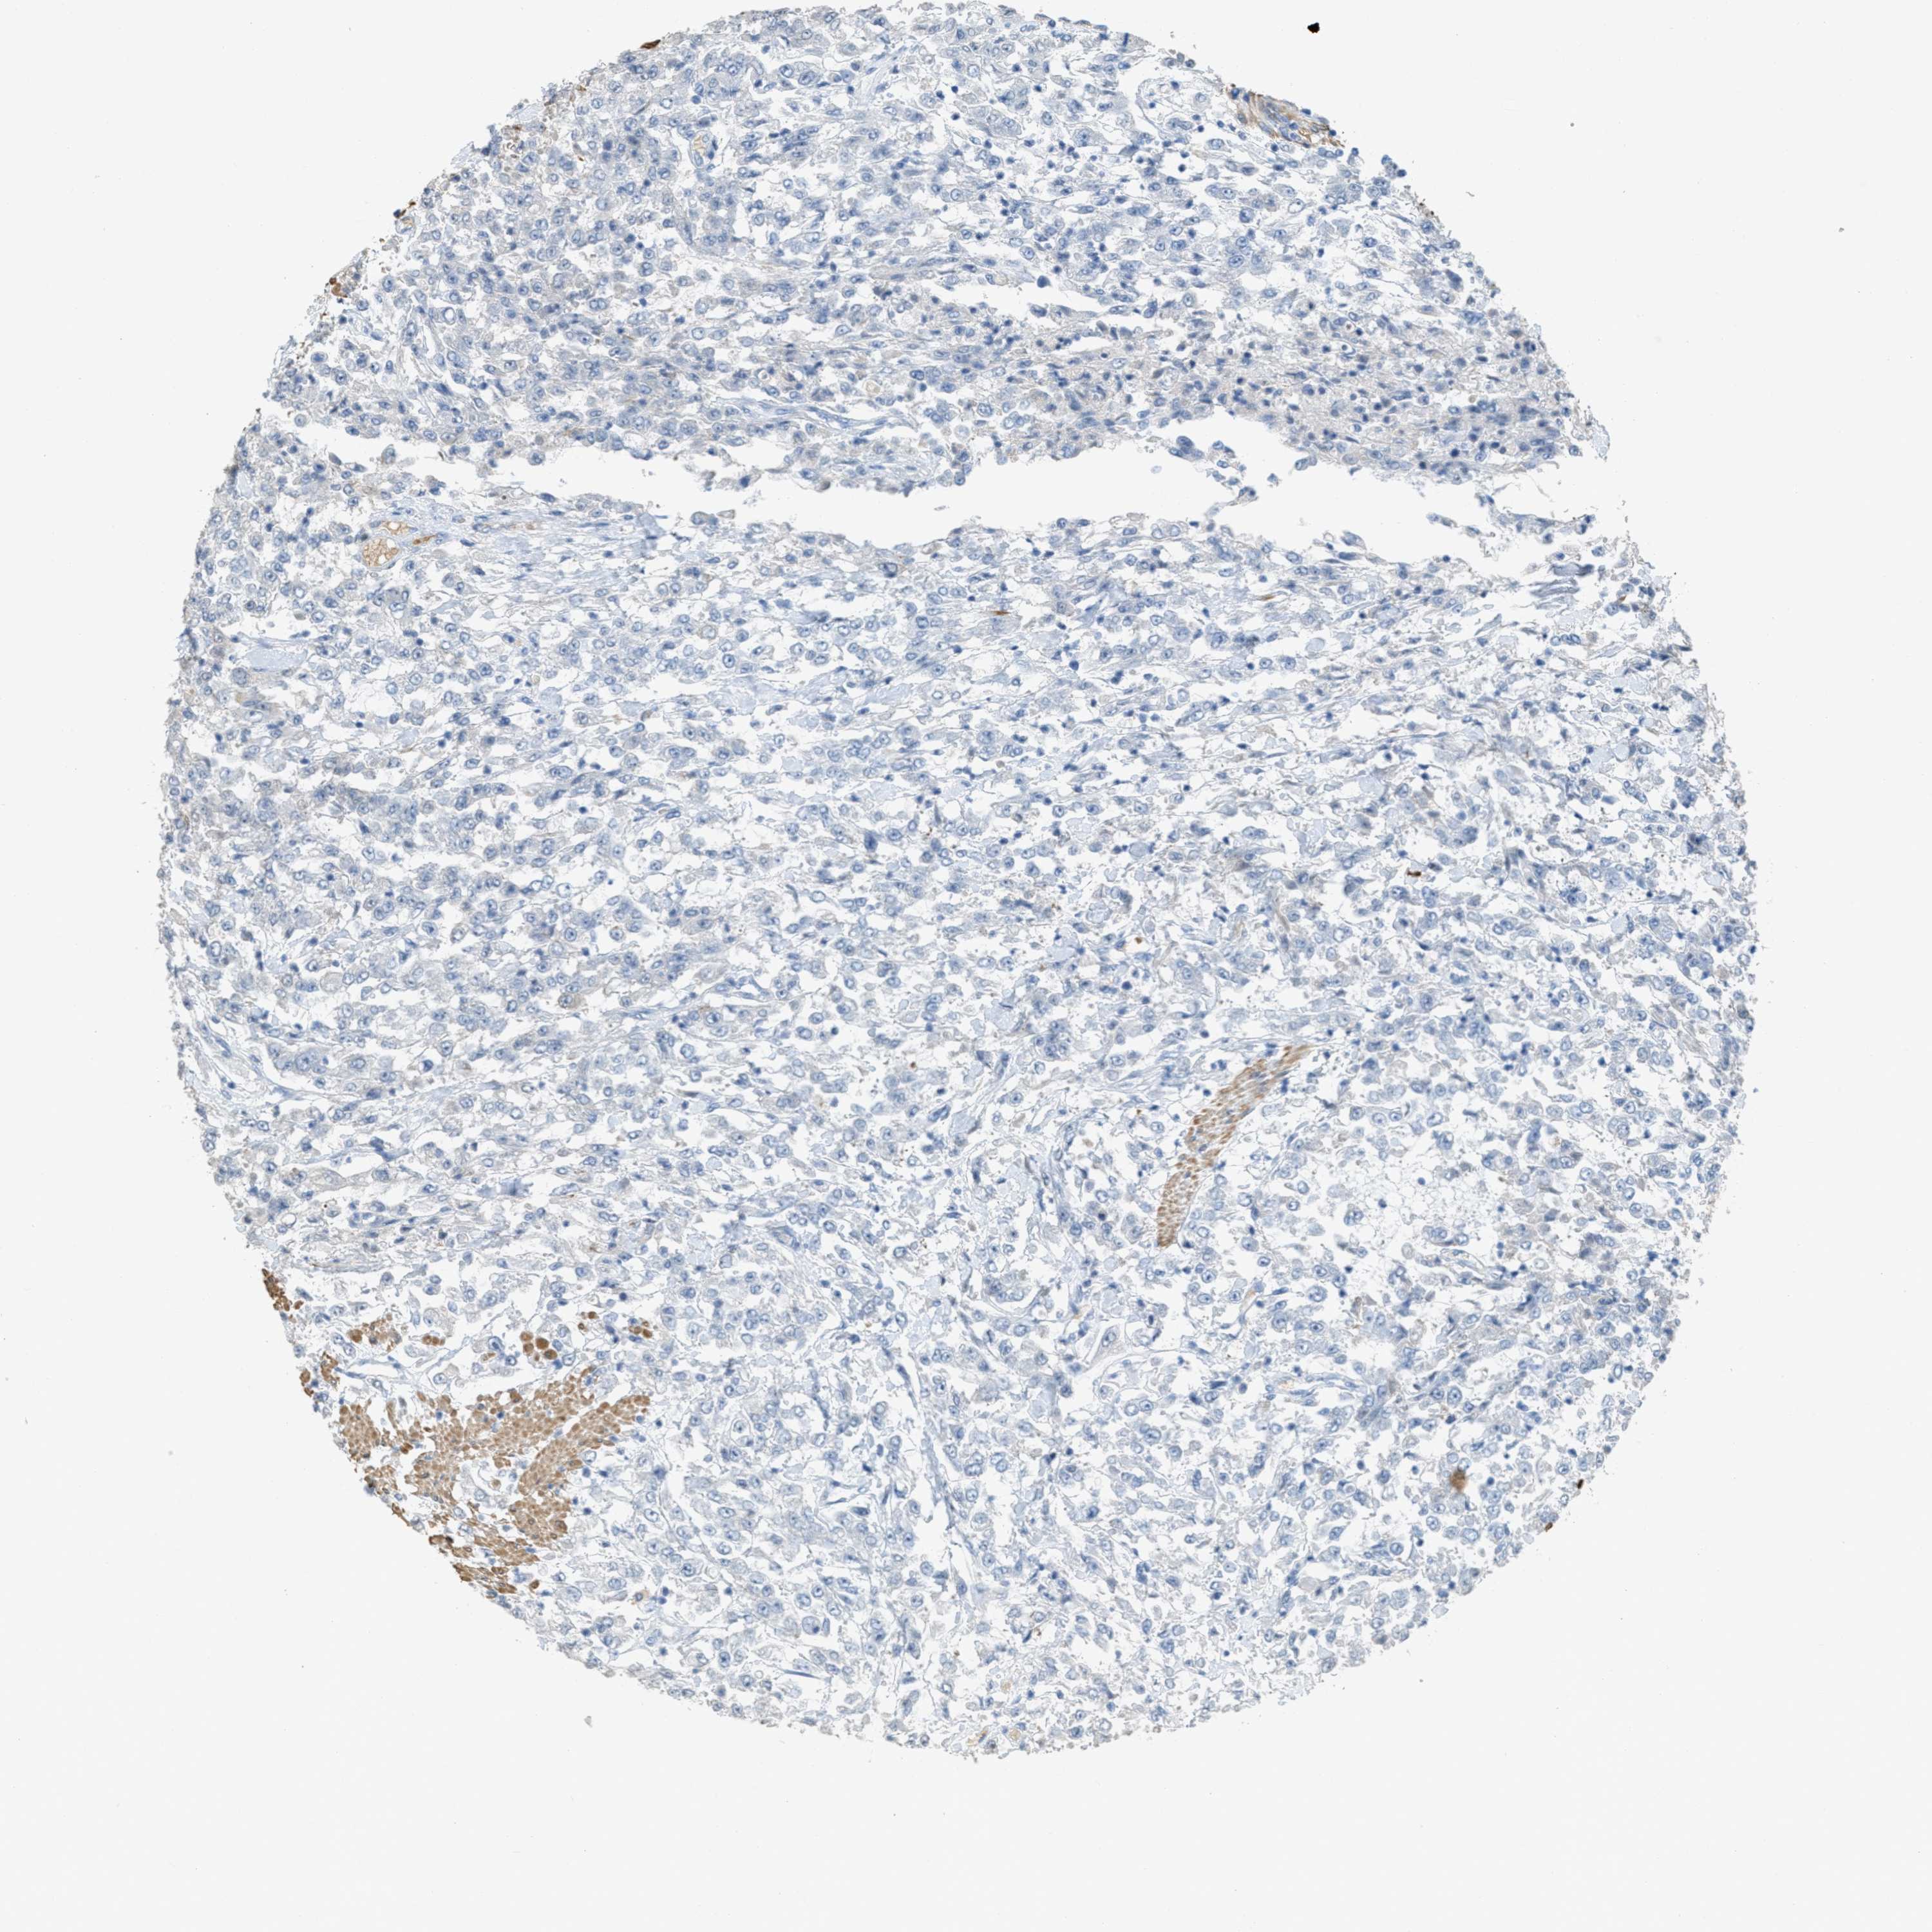

UROTHELIAL CANCER - Protein expressioni

A mouse-over function shows sample information and annotation data. Click on an image to view it in a full screen mode. Samples can be filtered based on level of antibody staining by selecting one or several of the following categories: high, medium, low and not detected. The assay and annotation is described here.

Note that samples used for immunohistochemistry by the Human Protein Atlas do not correspond to samples in the TCGA dataset.

Antibody stainingi

Antibody staining in the annotated cell types in the current human tissue is reported as not detected, low, medium, or high, based on conventional immunohistochemistry profiling in selected tissues. This score is based on the combination of the staining intensity and fraction of stained cells.

Each image is clickable and will lead to virtual microscopy that enables deeper exploration of all samples and also displays staining intensity scores, fraction scores and subcellular localization as well as patient and tissue information for each sample.

Antibody HPA017642

Staining

High

Medium

Low

Not detected

Intensity

Strong

Moderate

Weak

Negative

Quantity

>75%

75%-25%

<25%

None

Location

Nuclear

Cytoplasmic/membranous

Cytoplasmic/membranous,nuclear

Urothelial carcinoma, Low grade

Urothelial carcinoma, High grade